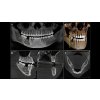

Špičkové 2D / 3D zařízení pro praxe s porozuměním nejnovějším technologiím a pro ty, kteří prostě chtějí více.Direct Conversion Sensor (DCS - senzor s přímou konverzí) přinesl revoluci do standardů panoramatického zobrazování - přináší jedinečnou ostrost. Technologie Sharp Layer poskytuje panoramatické snímky s automatickým zaostřováním, a to i v obtížných případech. Orthophos SL zaručuje snadné použití díky automatickému polohování, intuitivnímu ovládání s EasyPad a nabízí individuálně nastavitelné podsvícení pro exkluzivní vzhled a pocit.

Direct Conversion Sensor (DCS - senzor s přímou konverzí) přinesl revoluci do standardů panoramatického zobrazování. Rentgenové snímky přeměňovány přímo na elektrický signál a nedochází ke ztrátě signálu v důsledku konverze světla jako je tomu u běžných systémů. Výsledkem jsou snímky s extrémně vysokou a vysoce kontrastní úrovní ostrosti i při velmi nízké dávce záření.

Za použití příslušného senzoru získáte laterální a symetrické předozadní ap/pa kefalo snímky i snímky zápěstí. V případech retinovaných zubů se můžete vrátit zpět k výhodám 3D rentgenů a stanovit jejich přesnou lokaci.